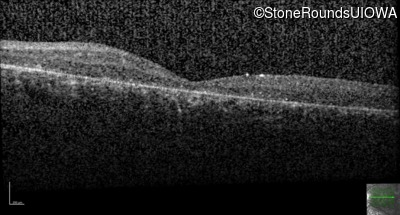

Optical Coherence Tomography - Right - 5/200

Exemplar / OCT Stack